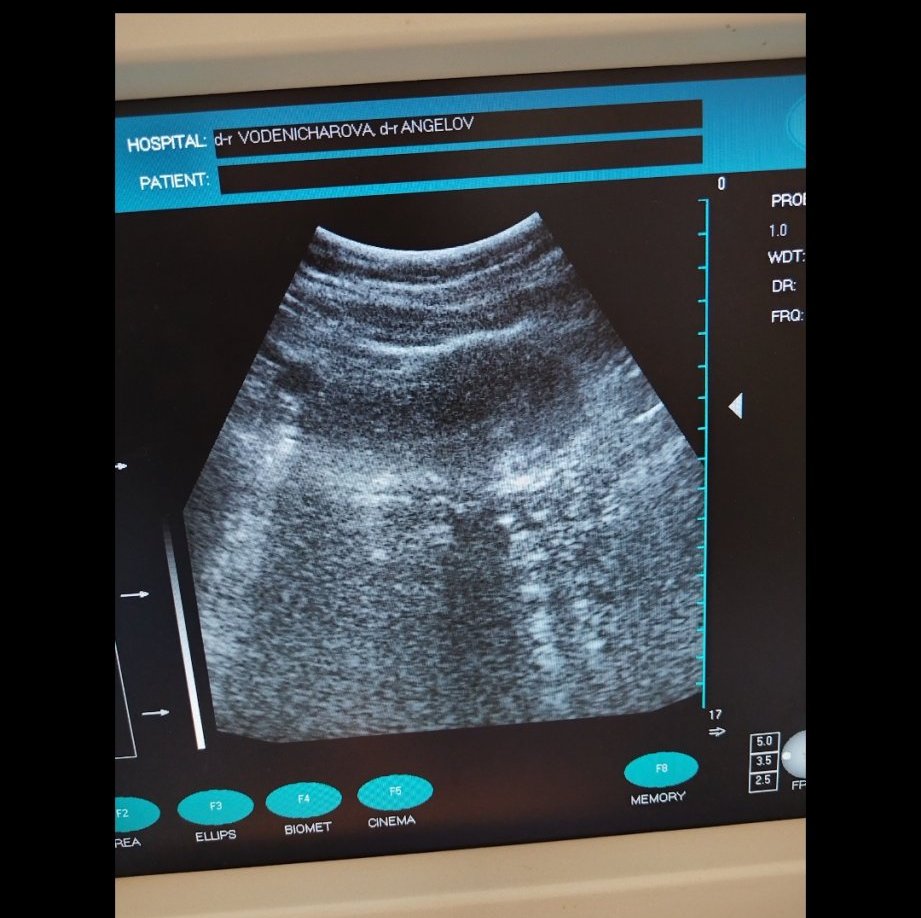

И още един въпрос тука дали е минала овулация

Според вас тука минала ли е овулацията